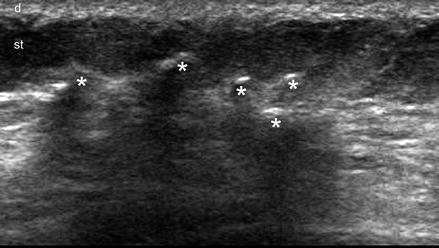

Ultrasound Of The Subcutaneous Tissue | SpringerLink

ultrasound subcutaneous tissue fig

Ultrasound subcutaneous tissue fig. Splint broken aid bone leg cast pad create fracture rigid form stack. Indirect edges bother rather rough didn